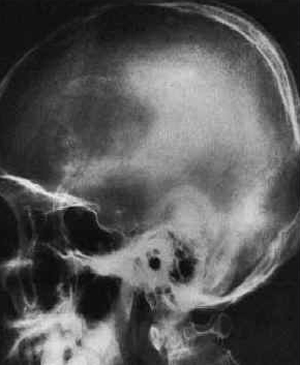

두개지방종 (Intracranial lipoma)

지방종(lipoma)드문종양으로서 임상증상은 나타 내지 않은 것도 있으며 부검시 우연히 발견되는 경우가 많다

정중선상에서 발생하는 것이 많으며 뇌량부(region of corpus callosum)에 가장 많다

뇌량외에 측내실맥락총(choroids plexus of lateral ventricle), 회백용기(tubercinereum), 사구 체부분(glomerular part)등에 호발된다